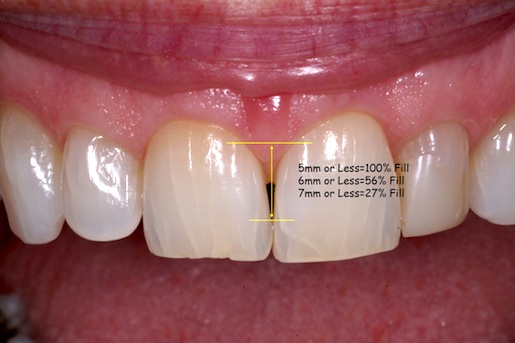

How do you know? One factor to keep in mind that has been researched in the past and is often referenced is the contact point to bone height [1]. Here are some numbers to consider the next time you’re trying to manage the papilla:

- 5mm or Less from Contact Point to Height of Bone = 100% fill

- 6mm or Less from Contact Point to Height of Bone = 56% fill

- 7mm or Less from Contact Point to Height of Bone = 27% fill